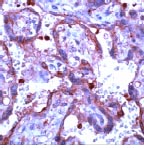

Immunohistochemistry (Formalin/PFA-fixed paraffin-embedded sections) - HRP Anti-MMP9 antibody [EP1255Y] (AB194316)

IHC image of MMP9 staining in a section of formalin-fixed paraffin-embedded human lung adenocarcinoma*. The section was pre-treated using pressure cooker heat mediated antigen retrieval with sodium citrate buffer (pH6) for 30mins, and incubated overnight at +4°C with ab194316 at a working dilution of 1/500. DAB was used as the chromogen (ab103723), diluted 1/100 and incubated for 10min at room temperature. The section was counterstained with haematoxylin and mounted with DPX. The inset negative control image is taken from an identical assay without primary antibody.

For other IHC staining systems (automated and non-automated) customers should optimize variable parameters such as antigen retrieval conditions, primary antibody concentration and antibody incubation times.

*Tissue obtained from the Human Research Tissue Bank, supported by the NIHR Cambridge Biomedical Research Centre